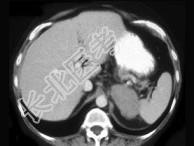

- 单项选择题女,47岁, 满月脸、向心性肥胖伴高血压1个月,请结合所提供图像, 作出诊断 ( )

A、左肾上腺腺瘤

B、左肾上腺腺癌

C、左肾上腺转移瘤

D、左肾上腺嗜铬细胞瘤

E、左肾上腺增生